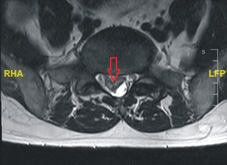

核磁共振的橫切面:可以看到明顯的椎間盤突出(箭頭處)造成神經壓迫